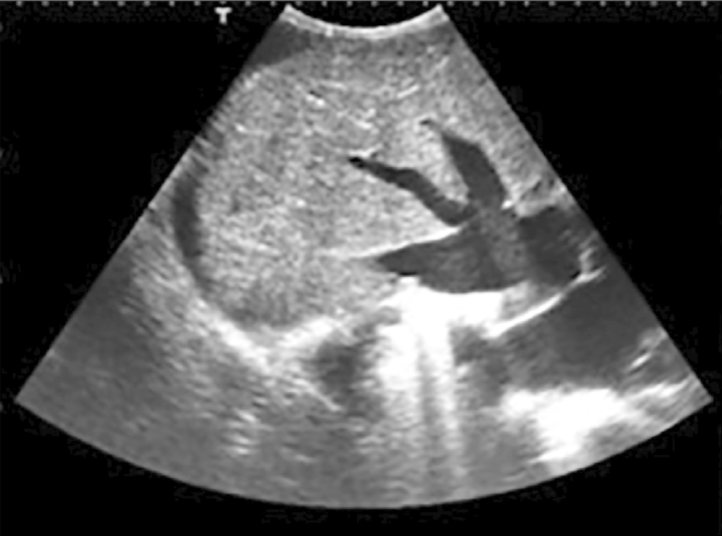

Constrictive pericarditis 2D findings:

thick calcific pericardium

normal size ventricle

enlarged atria

septal (IVS + IAS) bulge**

toward left during inspiration

“bound down” appearance of free walls

best seen A4C

dilated IVC + HV’s

no collapse w/ inspiration

Goose Foot Sign**